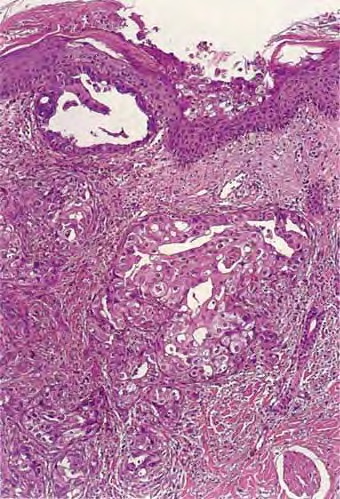

metastasis